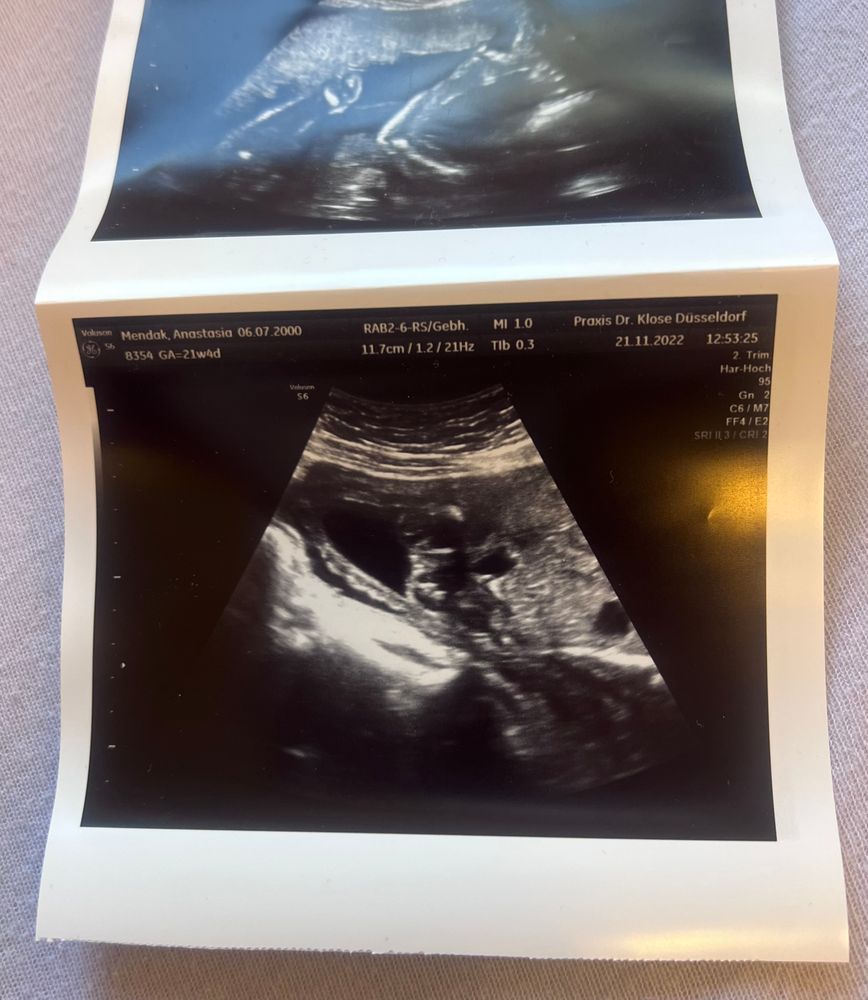

Почти закончился 6 месяц беременности а мне так и не могут сказать кто у меня родится. Через пару дней на узи, но не факт что скажут, старый аппарат и врач скорее не опытный. Я сейчас нахожусь на 25 неделе. Последнее фото было месяц назад на 21 неделе. На первом узи сказали что 80% мальчик(1фото). На втором узи сказали что ничего непонятно. На третьем сказали что возможно девочка, но ничего не видно. Помогите, пожалуйста, определить пол🐰

По таким фото не видно (ракурс и мелкие). Делают для точности узи попой снизу, чтобы видно было, что между ножек...странно,писюн не заметить, может, и правда тогда, пол женский. Но это всё домыслы. Сделайте в другом месте узи

Хотя знаете, мне на самом нижнем кажется, что девочка. Там похоже на "кофейное зёрнышко ".

У вас фото какие-то не удачные , в том смысле , что на них не видно пол, даже предположить не возможно. Я на последних двух вообще не пойму что изображено.